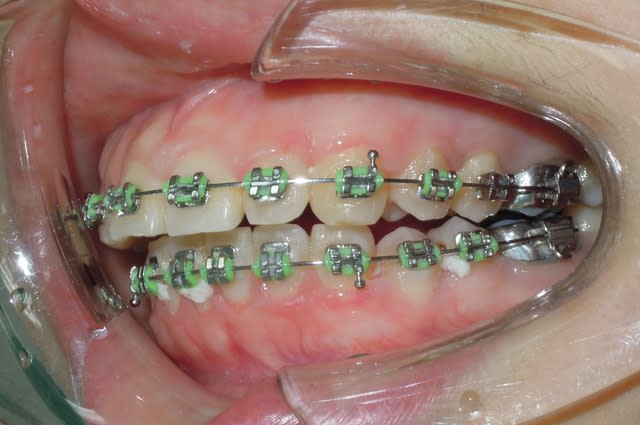

Patiente reçut en début d'année.

L'examen des éléments clinique montre qu'elle était border line extraction.

Vue que le profile et l’esthétique était correct, les enseignant on décider de commencer dans une optique de non extraction et de réévaluer a la fin de l'étape d'alignement.

Le traitement se déroule normalement.